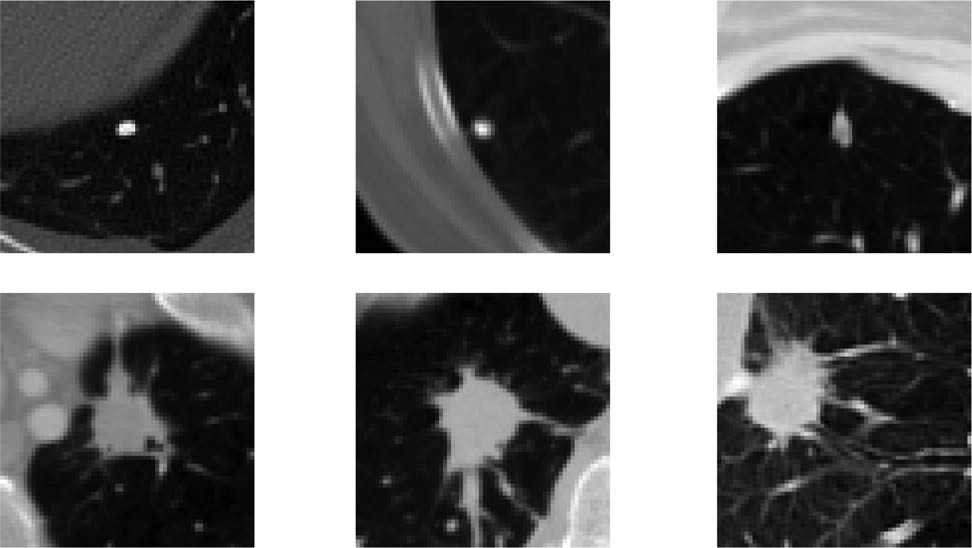

Lung cancer, with its high incidence and mortality rates, necessitates early diagnosis to improve survival outcomes. The classification of pulmonary nodules (as shown in Figure 1) as benign or malignant is essential for identifying potential malignancies and guiding treatment plans [1,2]. Traditionally, physicians evaluate these nodules using computed tomography (CT) images; however, this process can be time consuming and relies heavily on individual experience, which may affect both efficiency and accuracy. To address these challenges, computer-aided diagnosis (CAD) systems [3,4] have emerged as valuable tools that utilize advanced image processing and machine learning algorithms to automatically analyze CT images. By learning from extensive datasets to detect subtle imaging features, CAD systems leverage artificial intelligence to aid physicians in making faster and more accurate decisions, thereby significantly advancing the assessment of pulmonary nodules and enhancing modern medical imaging. Previously, many studies have indicated that machine learning methodologies play a crucial role in advancing the diagnostic accuracy of pulmonary nodules. For instance, Liu et al. developed a systematic approach that quantifies radiological traits and emphasizes semantic imaging features for predicting malignancy, resulting in enhanced predictive accuracy [5]. In another study, Ferreira et al.’s random forest algorithm demonstrated superior performance compared to other classifiers; notably, a decision tree using only two features achieved comparable sensitivity and specificity [6]. Meanwhile, Tu et al. effectively combined localized thin-section CT with radiomics feature extraction and machine learning to accurately classify early-detected pulmonary nodules, thereby reducing false positives while improving malignancy differentiation [7]. Yang et al. highlighted essential nodular features through a review focused on ground-glass opacity nodules, which were vital for developing effective prediction models [8]. Uthoff et al. contributed by standardizing perinodular features, while Yamada et al. improved classification accuracy with positron emission tomographic/CT images [9,10]. Furthermore, Chen et al.’s method had outperformed existing approaches in malignancy prediction; similarly, Liu et al.’s integration of CT findings with CEA levels yielded superior predictions [11,12]. Recently, many investigations have highlighted the effectiveness of deep learning techniques, particularly convolutional neural networks (CNNs), in detecting and classifying pulmonary nodules from CT scans. Wang et al. introduced a hybrid CNN model that enhanced malignancy risk assessment accuracy by integrating global and local features, surpassing traditional texture and shape-based methods [13]. Dou et al. developed a three-dimensional CNN that significantly reduced false positives by incorporating multilevel information, thereby improving detection efficiency [14]. Jin et al.’s deep 3D residual CNN further advanced lung cancer diagnosis by effectively targeting false positives [15]. Additionally, Feng et al. created a weaklysupervised CNN for automated nodule segmentation using image-level labels, successfully localizing nodules in CT images [16]. The integration of transfer learning has also played a crucial role; Zhao et al.’s approach outperformed other CNN strategies in distinguishing malignant from benign nodules [17]. Recent innovations such as the multiscale gradual integration CNN had shown significant improvements on datasets like LUNA16 [18]. Moreover, the growing body of literature indicated that hybrid models, attention mechanisms, and ensemble learning strategies – such as those developed by Yuans et al. and Xu et al. – were essential for achieving high sensitivity and accuracy in lung cancer risk assessment [19,20]. These advancements underscore the continuous evolution of deep learning methodologies within medical imaging, highlighting their potential to transform clinical practices and improve patient outcomes in lung cancer detection and management.

The samples of different pulmonary nodules.